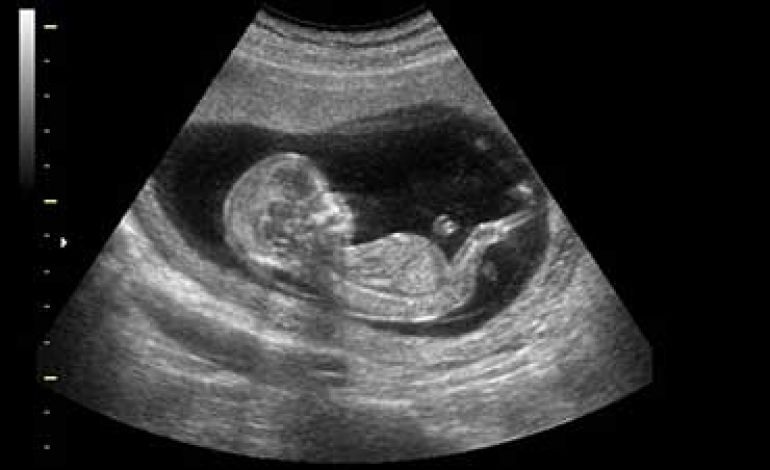

وی در پاسخ به نگرانی‌ها درباره انتقال بیماری قلبی به جنین گفت: انتقال بیماری قلبی مادر به جنین بسیار نادر است و عمدتاً در بیماری‌های مادرزادی قلب مطرح می‌شود. در این موارد نیز احتمال انتقال حدود ۴ تا ۵ درصد است و با انجام سونوگرافی قلب جنین در هفته‌های ۱۸ تا ۲۲ بارداری، امکان بررسی دقیق وجود دارد.

بیگدلو با تأکید بر ایمن بودن اکوکاردیوگرافی در دوران بارداری خاطرنشان کرد: این روش تشخیصی با استفاده از امواج اولتراسوند انجام می‌شود و هیچ خطری برای مادر یا جنین ندارد. اکوکاردیوگرافی بهترین و مطمئن‌ترین ابزار برای ارزیابی عملکرد قلب و دریچه‌ها در مادران باردار است.